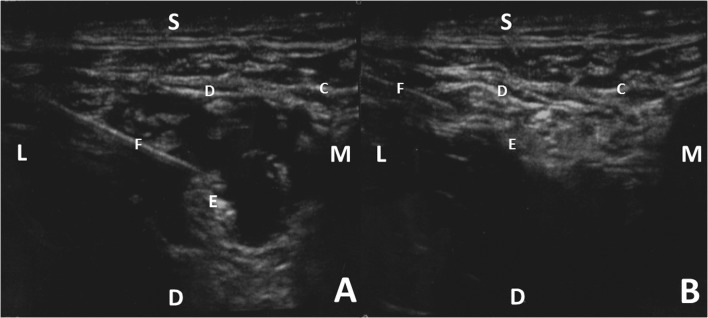

Fig. 2.

a The infiltration of local anesthesia around the femoral nerve. b The infiltration of local anesthesia deep to the fascia iliaca. S superficial, D deep, M medial, L lateral, C fascia lata, D fascia iliaca, E femoral nerve, F 22-gauge needle.

With the patient in the supine position, the operative extremity is draped to expose the inguinal region and superior thigh. After chlorohexidine preparation of the skin, a line is drawn with a marking pen from the anterior superior iliac spine to the pubic tubercle. The starting point is located approximately one third of the way on the line from the anterior superior iliac spine [21]. After placement of the ultrasound probe and identification of the ultrasonic regional anatomy including the fascia lata, fascia iliaca, and femoral artery, a 90-mm 22-gauge needle is advanced through the skin, subcutaneous fat, fascia lata, and just underneath the fascia iliaca. The femoral nerve, hyperechoic when visualized ultrasonically and located adjacent to the femoral artery, is identified just deep to the fascia iliaca (Fig. 1). At this point, approximately 20 mL of a mixture containing 20 mL of 0.5% ropivacaine and 20 mL of 2% lidocaine with 0.005 mg/mL of epinephrine is injected in the region around the femoral nerve (Fig. 2). The needle is then withdrawn laterally but with care to remain deep to the fascia iliaca at which point 10 mL is injected deep to the fascia iliaca (Fig. 2).